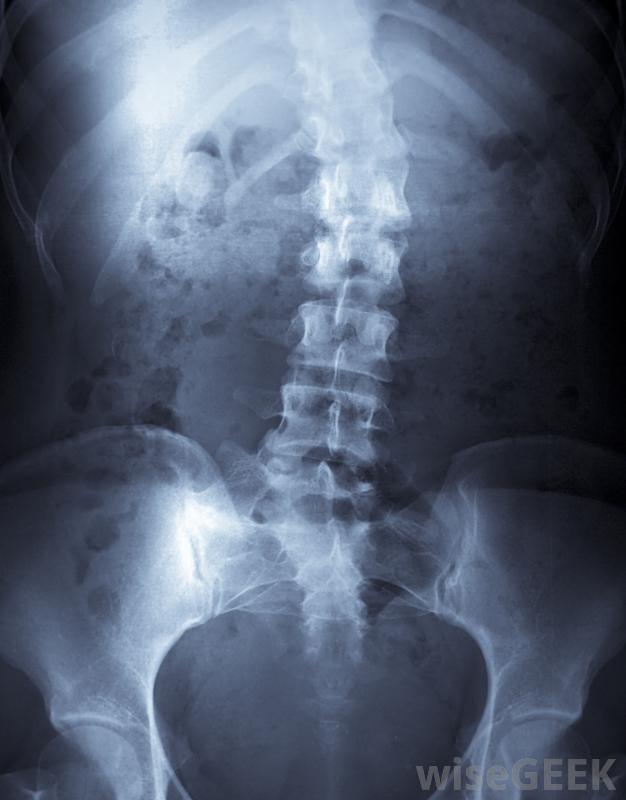

胸廓成形術包括縮短胸部特定部位的肋骨。對于脊柱側凸患者來說,這是一種相當常見的手術,因為它可以使脊柱側凸引起的肋骨隆起變小,也不那么嚴重。通常,病人在完成脊柱側凸矯正手術后,將進行胸腔成形術。胸廓成形術也可用于...

胸廓成形術包括縮短胸部特定部位的肋骨。對于脊柱側凸患者來說,這是一種相當常見的手術,因為它可以使脊柱側凸引起的肋骨隆起變小,也不那么嚴重。通常,病人在完成脊柱側凸矯正手術后,將進行胸腔成形術。胸廓成形術也可用于治療肺部疾病。例如,如果部分胸腔因結核、分枝桿菌或其他肺后疾病而感染,該手術可能是一種挽救生命的選擇胸廓成形術是脊柱側凸患者的常用治療方法,胸廓成形術可以減少由肋骨隆起引起的外部畸形,從而改善患者的整體外觀。此外,肋骨隆起可能相當疼痛,因此移除它可以減少或減輕與此相關的疼痛。例如,如果患者倚靠椅背時感到不適,去除肋骨隆起有助于降低不適程度。胸廓成形術包括縮短某些肋骨一般情況下,醫生會和病人討論胸廓成形術的部位,因為肋骨會縮短以減輕疼痛和減輕肋骨隆起,所以每個病人的情況都會被分析和考慮對于脊柱側凸的病例,肋骨的切除量取決于脊柱的曲線、駝峰的嚴重程度和大小。患者在完成脊柱側凸矯正手術后通常會進行胸腔成形術令人驚訝的是,在胸腔成形術完成后的兩到四個月內,肋骨或肋骨會重新生長并產生一個或多個新的肋骨。新的肋骨將與之前的肋骨一樣堅固,一旦愈合過程完成。不幸的是,如果脊柱彎曲繼續惡化,肋骨隆起可能會復發。因此,治療脊柱側凸非常重要,同時去除肋骨隆胸術后,大多數病人都戴一個支架來保護胸腔不受肋骨的傷害。這樣做可以防止肋骨摩擦胸腔內部器官,并減少胸腔積液的幾率,這就需要胸腔插管。基本上,雖然支架沒有什么作用,但它可以減少立即發生并發癥的幾率為了提高手術的效果。此外,無保護的胸壁在日常活動中幾乎沒有危險。當然,如果發生外傷,它可能會損壞胸壁。一個決定繼續前進的患者隨著胸廓成形術的進行,預計要在醫院呆四到八天。此外,完全康復可能需要幾個月的時間在進行這項手術之前,與一位聲譽良好的外科醫生討論所有問題和解決任何問題是很重要的。胸腔成形術可用于治療肺結核和其他肺部疾病。